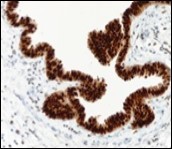

Immune Histochemical Elucidation

Epithelium of cutaneous ciliated cyst is immune reactive for pan cytokeratin (CKae1/ae3) antigens, epithelial membrane antigen (EMA), oestrogen receptors (ER), progesterone receptors (PR), Wilm’s tumour protein (WT-1) and paired box gene 8 (PAX8). Immune non reactivity is cogitated for S100, smooth muscle actin (SMA), carcino-embryonic antigen (CEA), desmin, thyroid transcription factor(TTF1), p63 and glial fibrillary acidic protein (GFAP).

Smooth muscle actin (SMA) is immune non reactive, thereby suggesting an absence of smooth muscle within the cyst wall. Intense immune reactivity can be cogitated within epithelial nuclei for oestrogen receptors (ER) and progesterone receptors (PR). Aforesaid immune reactions are indicative of Mullerian origin of cutaneous ciliated cyst.

Focal epithelial staining for periodic acid Schiff’s(PAS) stain is enunciated 4, 5. Pan cytokeratin (CKae1/ae3) are diffusely immune reactive.

Cutaneous ciliated cyst demonstrates immune reactivity to Dyein, akin to the reaction elicited in normal fallopian epithelium. Nevertheless, atypical locations of cutaneous ciliated cyst or those arising in males are immune non- reactive with oestrogen receptors (ER) and progesterone receptors (PR) on account of enunciated eccrine glandular epithelium. However, particular instances are immune reactive with carcinoembryonic antigen (CEA), p63, S100 and gross cystic fluid disease protein (GCFDP-15) 8, 9.

Figure 10.Cutaneous ciliated cyst with nuclear immune reactivity to progesterone receptors (18).

Figure 11.Cutaneous ciliated cyst with immune reactivity to cyto-keratin (19).

Figure 12.Cutaneous ciliated cyst with nuclear immune reactivity to oestrogen receptors (19).